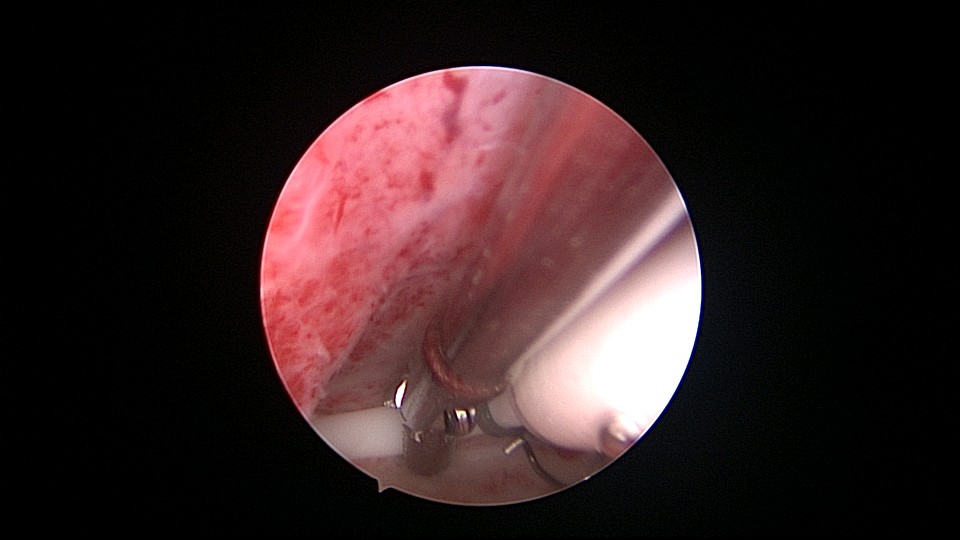

患者53岁,G3P1,顺产1次(产后大出血)。1年前因盆腔器官脱垂行阴道前后壁修补手术,同时行宫腔镜息肉切除手术,病检为增生反应子宫内膜伴出血。2025年2月,绝经2年,阴道出血半天,行宫腔镜检查及诊刮,放置曼月乐并固定,用曼月乐尾丝连接环与不锈钢挂钩,将挂钩插入宫底肌层固定,异物钳原位固定曼月乐,退出宫腔镜,结束手术。2025年4月复查B超曼月乐位置正常,环顶端距宫底1.1cm。病检为子宫内膜增生,不伴非典型增生。